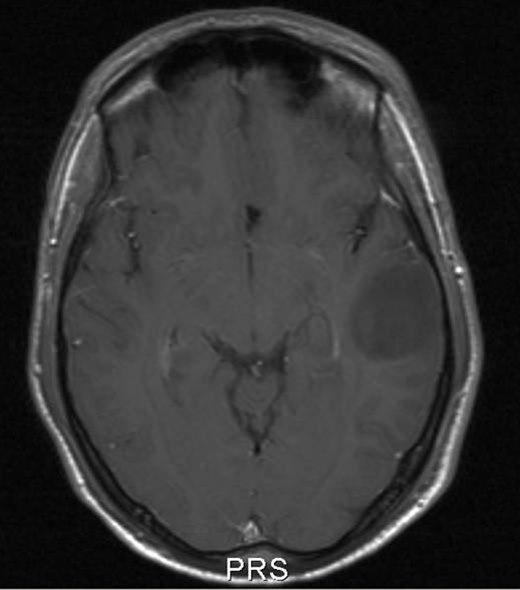

Lavgradig astrocytom, aksialt snitt

Lavgradig astrocytom WHO grad II

Gjengitt med tillatelse av Radiologisk avdeling, Universitetssykehuset Nord-Norge